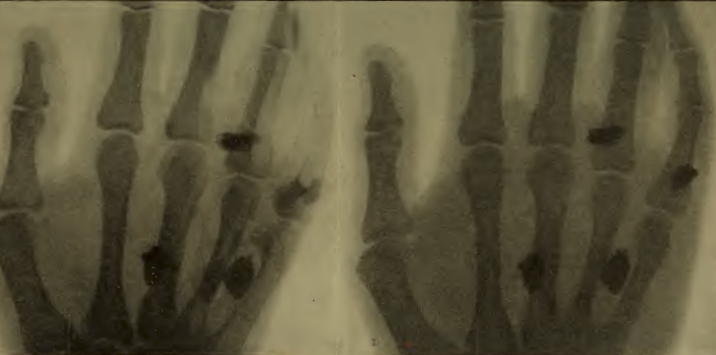

PLANCHE 7. — Radiographie d'un avant-bras. Fracture du radius avec perte de substance. A gauche: vue de face. A droite: vue de profil.

Les planches VI et VII reproduisent des radiographies de fractures suivant des documents originaux. On peut s'y rendre compte de la différence d'aspect d'images obtenues de face et de profil. Les planches VIII et IX représentent des fractures en voie de guérison, avec formation de cal.